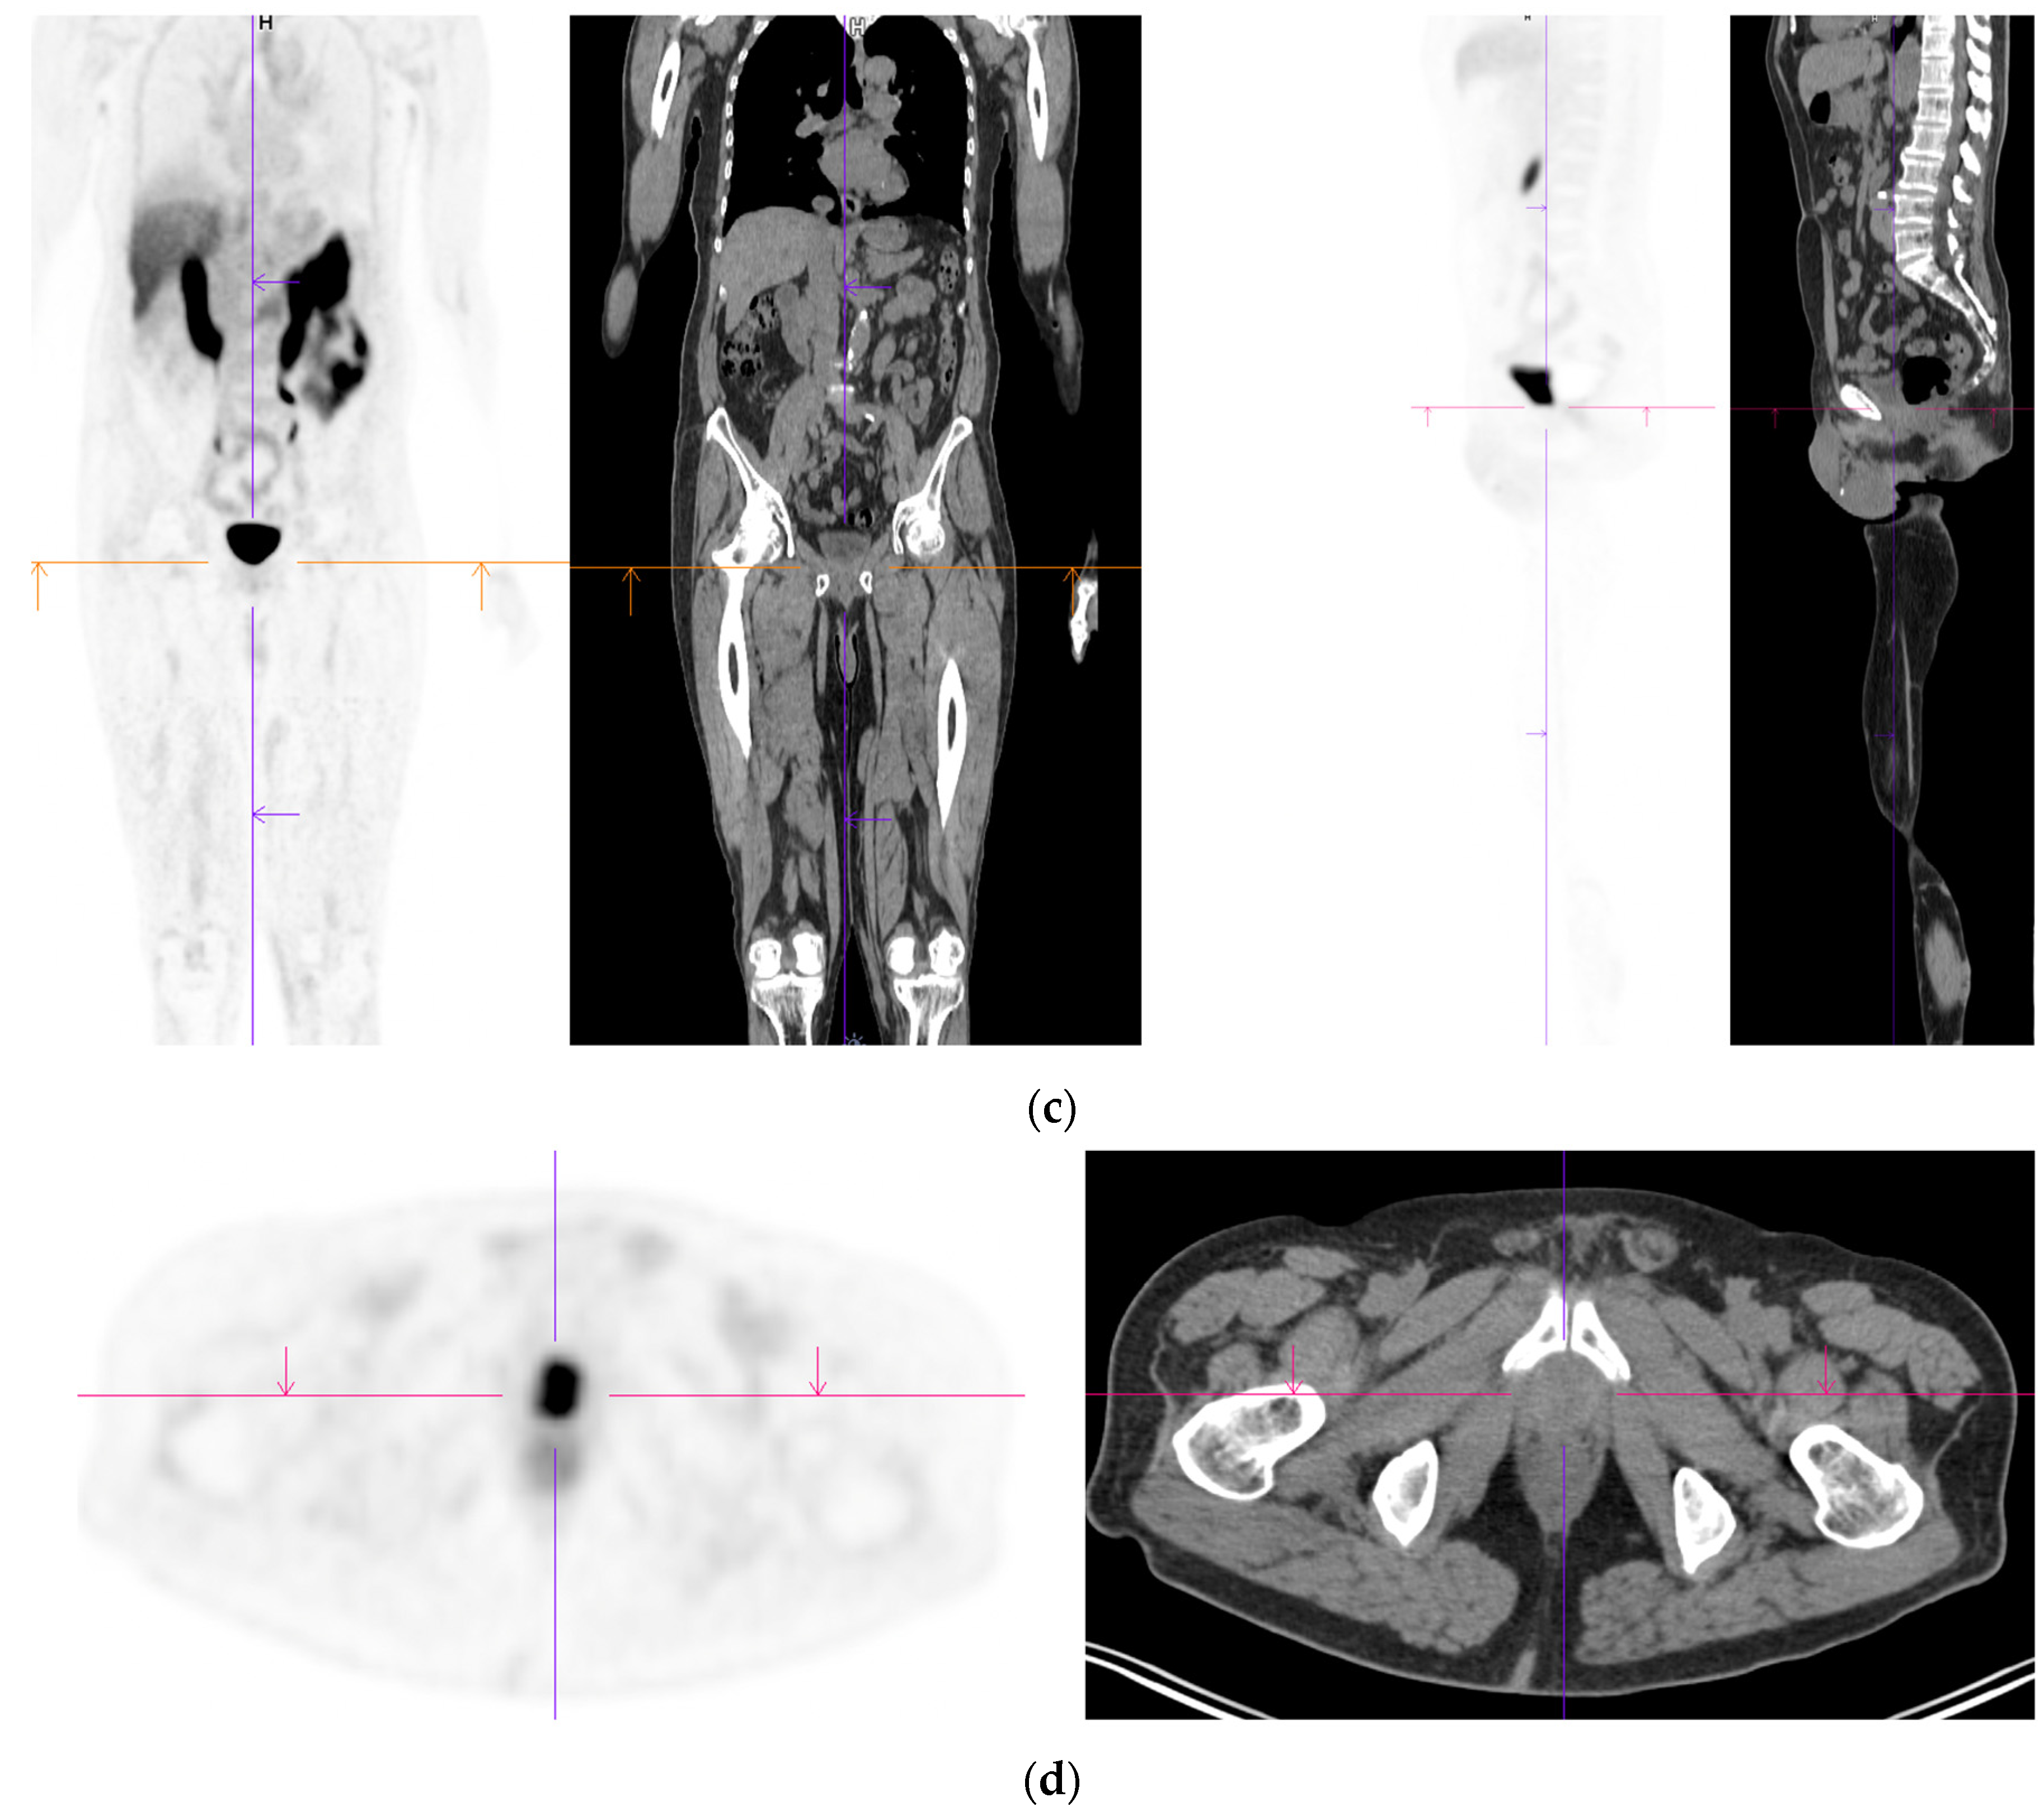

Figure 3.

Recurrent disease. 74 yr old M; radical prostatectomy 8 yrs prior; extensive para-aortic and upper pelvic lymph node involvement on CT; severe back pain; PSA 60. PSMA PET-CT: 68Ga-PSMA-216 MBq; uptake 48 min; BMI = 31.9; Wt 89 kg. (a,b): Coronal and sagittal images show bulky nodal disease with markedly increased uptake (SUV = 68.2) in abdomen and pelvis, hepatic metastases, multiple bony metastases in pelvis, lower limbs, sternum, ribs and vertebral column. (c): enlarged transaxial images of lower thorax/upper abdomen show tracer avid foci in segments 7 (SUV = 8.8), 4 (SUV = 8.7) of liver; X-hairs on lesion in right 10th rib, SUV = 14.6; CT on bone windows shows small region of sclerosis vs. extensive uptake on PET.